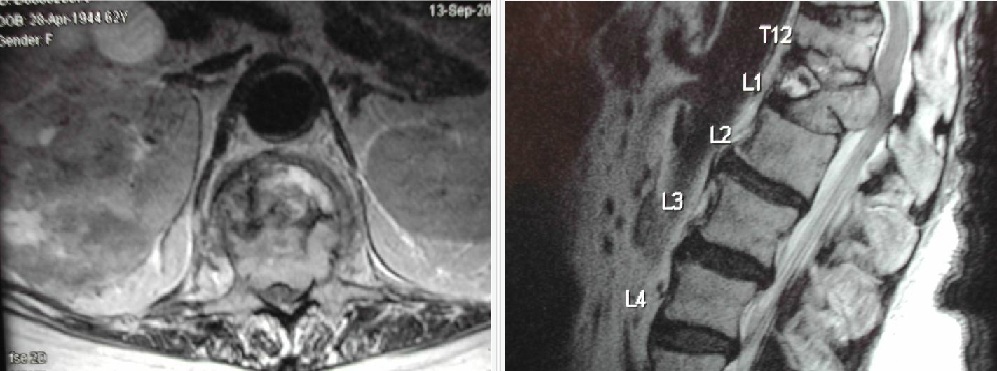

Seorang wanita 50 thn datang dgn riwayat 1 thn LBP progresif dan konstipasi. MRI menunjukkan massa sacral yg besar. Dia scr neurologis normal. Apakah langkah plg tepat yg selanjutnya dilakukan untuk menentukan terapi pasien ini?

A. Formal urodynamic studies

B. MRI dgn kontras di pelvis

C. Biopsi dgn CT pada massa

D. MRI of the skull base

E. Pemeriksaan proctoscopic untuk menilai integritas/ keutuhan

The differential diagnosis for this lesion includes diagnoses for which en bloc resection has been reported to provide the best chances of disease-free survival. Compared with intralesional resection, en bloc resection can be substantially more challenging and involve greater morbidity. A CT-guided biopsy of the lesion, with careful marking of the biopsy tract, can provide a tissue diagnosis prior to definitive surgical intervention in order to decide whether the lesion necessitates an attempt at en bloc resection. In this patient, a CT-guided biopsy demonstrated chordoma, a lesion best treated with en-bloc resection if feasible.

Seorang pria 60 thn datang dgn rasa sakit yg progresif di sakrum selama 6 bulan. MR menunjukkan lesi 8 cm di sakrum paling sesuai dgn chordoma. Apakah pilihan terapi yg plg tepat dan terbaik pada pasien ini yg dikaitkan dgn hasil jangka panjang terbaik?

A. Dekompresi tumor intralesi untuk meringankan nyeri dan memungkinkan untuk diagnosis jaringan diikuti dgn sinar proton radioterapi

B. Biopsi dgn CTdari lesi untuk mengkonfirmasi diagnosis diikuti en bloc reseksi dari lesi termasuk reseksi dari biopsy tract

C. Biopsi dgn CTdari lesi untuk mengkonfirmasi diagnosis diikuti sinar proton radioterapi

D. Sinar proton radioterapi saja tanpa biopsy untuk menghindari pembenihan tumor di saluran biopsy mengingat hasil MR dari chordoma sangat spesifik

All sacral tumors must have proper histological confirmation prior to en bloc resection or radiotherapy. Incisional biopsy or intralesional resection increases the risk of local recurrence of a chordoma. Therefore, transcutaneous CT-guided trocar biopsy is preferred to open biopsy to minimize the risk of contamination of normal tissues by tumor. The biopsy tract should be planned to be included within the subsequent resection margins. En bloc resection of primary spine tumors with disease-free margins is achievable and provides the best long-term survival for patients. Less than en bloc resection is associated with an almost 100% tumor recurrent rate, even after radiotherapy.